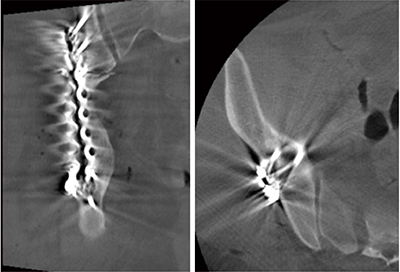

当センターの寛骨臼骨折に対する観血的骨整復術は,X線血管撮影装置を搭載したハイブリッド手術室で行われる。寛骨臼骨折は直視下での整復や転位の確認が困難なため,術中CBCTが骨折部の関節適合性の評価に有用となる。手術は術前にシミュレーションした3Dプランニングを確認しながら進行する。プレートを固定後,術中CBCTを撮影し速やかにmulti planar reconstruction(MPR)画像を表示する(図5)。モニタにて関節内への穿破の有無,坐骨方向への確実なスクリュー挿入,前柱骨片の整復位などの評価を,執刀医だけでなく助手や診療放射線技師を含めて行う。術中に3Dプランニングと比較し評価を行うことで,プレート位置やスクリュー長の修正,前方アプローチの必要性を判断することが可能になっている。これらに問題がなければ閉創となる。

図5 術中CBCTによるMPR画像